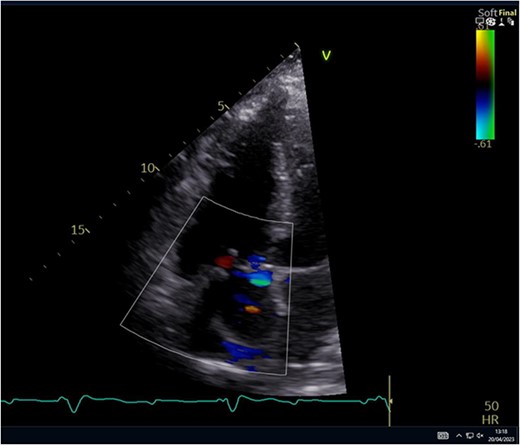

The leaflet was excised and a 27 mm Mitral Magna Ease tissue valve was implanted. He was successfully weaned off cardiopulmonary bypass and decannulated off ECMO in sinus rhythm. Post-operative ECHO showed a well seated and functioning TV prosthesis (Fig. 4).